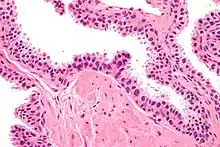

Micrograph showing high-grade prostatic intraepithelial neoplasia. H&E stain.

Microscopically, PIN is a collection of irregular, atypical epithelial cells. The architecture of the glands and ducts remains normal. The epithelial cells proliferate and crowding results in a pseudo-multilayer appearance. They remain fully contained within a prostate acinus (the berry-shaped termination of a gland, where the secretion is produced) or duct. The latter can be demonstrated with special staining techniques (immunohistochemistry for cytokeratins) to identify the basal cells forming the supporting layer of the acinus. In prostate cancer, the abnormal cells spread beyond the boundaries of the acinus and form clusters without basal cells. In HGPIN, the basal cell layer is disrupted but present. PIN is primarily found in the peripheral zone of the prostate (75-80%), rarely in the transition zone (10-15%) and very rarely in the central zone (5%), a distribution that parallels the zonal distribution for prostate carcinoma.[7]